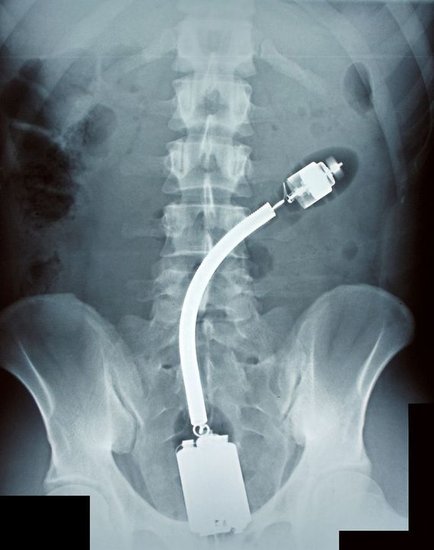

- Mithilfe von Röntgenaufnahmen entdecken Ärzte hin und wieder unterschiedliche Dinge, wie Nägel, Scheren, Diamantenringe, Flaschen und sogar Quietsche-Entchen. Merkwürdig ist, dass manche der Patienten angeblich nicht wissen, wie diese Dinge in ihre Körper gelangten...